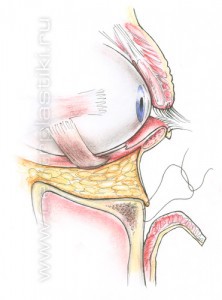

Рис. 6 Мышцу, аккуратно приподнимают и отделяют до края глазницы. Рис.7. Жировые «грыжи» опускаются вниз за край глазницы и фиксируются к надкостнице несколькими нитями, Рис. 8-9 таким образом, удается заполнить слезную и веко-щечную борозды Рис. 10.

Рис. 9 Через боковую часть разреза выполняется отделение надкостницы от костей в проекции средней зоны лица вниз до крыла носа, обычно для этого используются эндоскопические инструменты. Рис. 11 Мобилизованные ткани прошиваются в верхненаружном углу и фиксируются к надкостнице выше наружного угла глаза. Рис. 12 Выполняется миопексия (фиксация мышцы окружающей глаз) Рис. 13 и кантопексия (фиксация наружного угла глаза), Рис. 14 затем удаляется избыток кожи Рис. 15. Этим достигается правильное положение глазной щели и удается добиться разглаживания мелких морщин. В конце операции кожная рана зашивается косметичным внутрикожным швом.